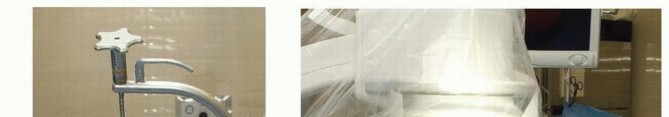

arthroscope is approximately 2.7 mm in diameter, and even smaller scopes may be used if desired. In addition, a small joint shaver (3.5 mm or less) is useful to clear fracture debris and hematoma. The ideal timing for arthroscopic-assisted fixation of distal radius fractures is 3 to 10 days following injury. 13 Earlier attempts at fixation may be complicated by soft tissue swelling and troublesome bleeding, obscuring visualization. After 10 days, the fracture fragments start to become sticky and more difficult to percutaneously elevate and reduce. ## Positioning Arthroscopic-assisted fixation of distal radius fractures may be performed with the arm suspended vertically in a traction tower, horizontally in a traction tower, or with finger traps applied attached to weights hanging over the edge of the hand table. Wrist arthroscopy in the horizontal position may make it easier to simultaneously monitor the reduction fluoroscopically and place hardware. However, it does not allow for simultaneous volar access to the wrist. Suspending the wrist in a vertical position with a traction tower allows simultaneous access to both the volar and dorsal aspects of the wrist. This is particularly useful when wrist arthroscopy is used as an adjunct to volar plate fixation of the distal radius fracture. A new traction tower has been designed to allow simultaneous evaluation of the intra-articular reduction of the distal radius arthroscopically and fluoroscopically ( FIG 2A). The surgeon may stabilize a comminuted fracture of the distal radius with a plate, and simultaneously evaluate the articular reduction arthroscopically. The traction tower allows for traction of the wrist in either the vertical or horizontal planes, depending on the surgeon's preference ( FIG 2B). ## Approach The wrist is suspended in a traction tower, and the standard dorsal 3-4 viewing portal, 4-5 or 6R working portal, and 6U inflow portal are made.

### FIG 2 • A. This traction tower uses a suspension bar at the side rather than at the center of the wrist. This allows easy fluoroscopic evaluation of the fracture reduction, with simultaneous full access to the volar and dorsal aspects of the wrist. B. The tower can be flexed into a horizontal position for surgeons who prefer to treat distal radius fractures in that position. It is difficult to palpate the normal extensor tendon landmarks for traditional wrist arthroscopy in patients who sustain a fracture of the distal radius because of swelling. 17 However, the bony landmarks usually can still be palpated. These bony landmarks include the bases of the metacarpals, the dorsal lip of the radius, and the ulnar head. The 3-4 portal is made in line with the radial border of the long finger. It is very useful to place an 18-gauge needle into the proposed location of the 3-4 portal before making a skin incision. If the portal is placed too proximal, the arthroscope may be placed within the fracture pattern itself. If it is placed too distal, it can injure the articular surface of the carpus. Once the precise ideal location of the portal is located, the portal is made by pulling the skin with the surgeon's thumb against the tip of a no. 11 blade. Blunt dissection is carried down with a hemostat, and the arthroscope, with a blunt trocar, is introduced into the dorsal 3-4 portal. This technique decreases potential injury to cutaneous nerves. Thorough irrigation of the joint is necessary to wash out fracture hematoma and debris and improve visualization. Inflow may be provided through the arthroscope cannula or separately through a 14-gauge needle into the 6U portal. Use of a separate 6U inflow portal is recommended. The small joint arthroscopy cannula does not allow as much space between the cannula and the arthroscope, limiting the amount of flow through the cannula. Outflow to the wrist is provided through intravenous extension tubing connected to the arthroscope cannula. The 4-5 working portal is made in line with the mid-axis of the ring metacarpal. Alternatively, the 6R working portal is made just radial to the palpable extensor carpi ulnaris tendon. An 18-gauge needle is placed into the joint and should lie just distal to the articular disc. A 4-5 or 6R portal usually is located just proximal to the 3-4 portal because of the natural radial slope of the distal radius.